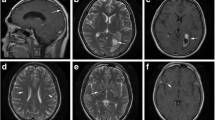

There were 48 patients in the NSDB group and 72 in the SDB group. The patients in the NSDB group were characterized by normal brain imaging (Fig. 1A). The patients in the SDB group were primarily characterized by CM-related brain damage(Fig. 1B). The characteristics of the NSDB and SDB groups are summarized in Table 2. In patients with CM alone, the BMI of patients in the SDB group was significantly lower than that in the NSDB group (Table 2).

MRI in NSDB and SDB groups: A MRI in NSDB group; B MRI in SDB group (NVM); C MRI in SDB group (VM); red arrows cryptococcal meningitis-related brain damage, yellow arrows ventriculomegaly. MRI magnetic resonance imaging; NSDB non-structural damage of the brain; SDB structural damage of the brain; NVM non-ventriculomegaly; VM ventriculomegaly

Characteristics of Patients with Alterations in Cerebral Ventricles

In the SDB group, there were 27 patients with and ventriculomegaly (VM; Fig. 1C). The patients in the SDB group were divided into the non-VM (NVM) and VM groups. The general characteristics of patients in these groups are enumerated in Table 5. The age of patients in the NVM group (45.27 ± 12.45 years) was significantly lower than that in the VM group (55.89 ± 14.30 years; P < 0.01). The results of the analysis of the characteristics of CSF and PB in these two groups are summarized in Table 6. Compared with the NVM group, the levels of PB-Hb (P < 0.05), PB-ALB (P < 0.05), and PB-K (P < 0.01) were significantly decreased in the VM group, and the levels of PB-UA (P < 0.05) were significantly increased in the VM group. Of note, hypokalemia is recognized as a common side effect of AmpB [33]. To ascertain whether AmpB led to alterations in the peripheral metabolism, the patients in the SDB group were divided into two groups, namely, the non-received AmpB group and the received AmpB group. The results revealed no significant difference in the levels of PB-K, PB-Hb, PB-ALB, and PB-UA (Table 7).